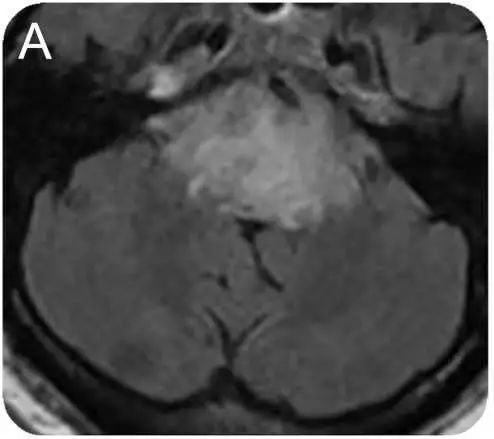

52岁,丙型肝炎患者,进行肝移植治疗肝硬化后使用免疫*制剂抑**等(他克莫司、霉酚酸酯、强的松)治疗。治疗3个月后出现间歇性头痛,复视(多为下视时出现),步态不稳,无全身症状。查体:血压136/73mmHg。眼球震颤,步态共济失调,腱反射正常。

答案:他克莫司相关神经毒性致脑干损伤。

补充辅助检查:血沉阴性,C-反应蛋白,艾滋病毒、半乳甘露聚糖、1,3-b-D-葡聚糖、隐球菌,结核均阴性。脑脊液中有1个白细胞,蛋白质101 mg/dL,革兰氏阴性染色,细菌性真菌培养,EB病毒,巨细胞病毒,单纯疱疹病毒,人类疱疹病毒6型,JC病毒,以及寡克隆带均阴性。免疫球蛋白G指数为正常。胸片呈阴性。脑PET扫描未发现PET摄取异常。在患者住院期间,他克莫司的治疗剂量为6.3~9.0ng/ ml。经治医生不排除他克莫司导致脑干脑炎的可能,并将药物改为环孢菌素。患者入院2周和6周各进行了一次MRI 检查,结果显示脑干病变较前好转 (图B、C)。6个月后随访,患者的神经系统检查和MRI 均未见明显异常。B为他克莫司停药后2周MRI。C为 6周后脑磁共振Flair图像。

他克莫司是抑制神经钙蛋白磷酸酶活性和T淋巴细胞化的免疫*制剂抑**。可引发一系列神经系统的不良反应,包括轻微头痛、震颤痫性发作、皮质性失明和昏迷,且不良反应的发生与他克莫司剂量无相关性。

当患者出现T2及Flair序列的脑桥高信号时,要考虑到他克莫司神经毒性导致脑干脑炎的可能。